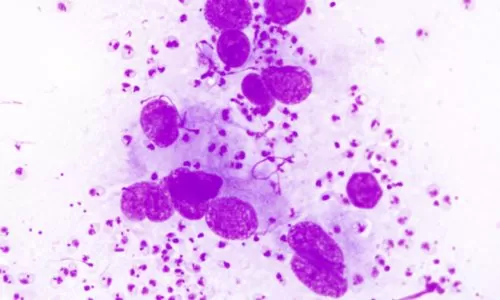

Citopatologia: coleta, avaliação microscópica e interpretação de resultados.